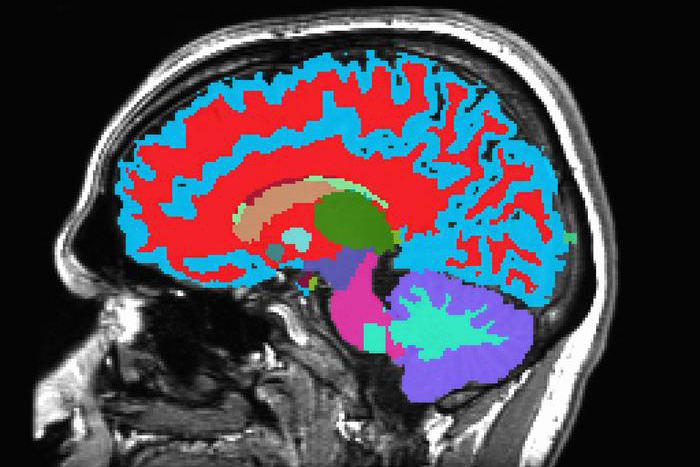

Most of the study participants also had an MRI scan at age 45. In the new study, the team combined the Pace of Aging scores with the MRI scan data. They developed a new aging measurement, called Dunedin-PACNI, based on the brain scans alone. They then tested the new tool with data collected on thousands of people from other studies.